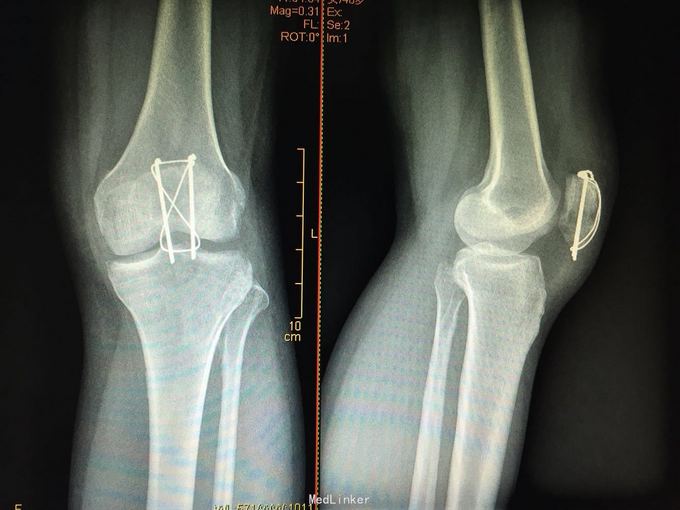

髌骨骨折切开复位克氏针张力带内固定

术后1年骨折已愈合、功能良好,予取出内固定。 讨论 髌骨骨折除了经典克氏针张力带,大家还做那些术式及内固定,术后如何行功能锻炼